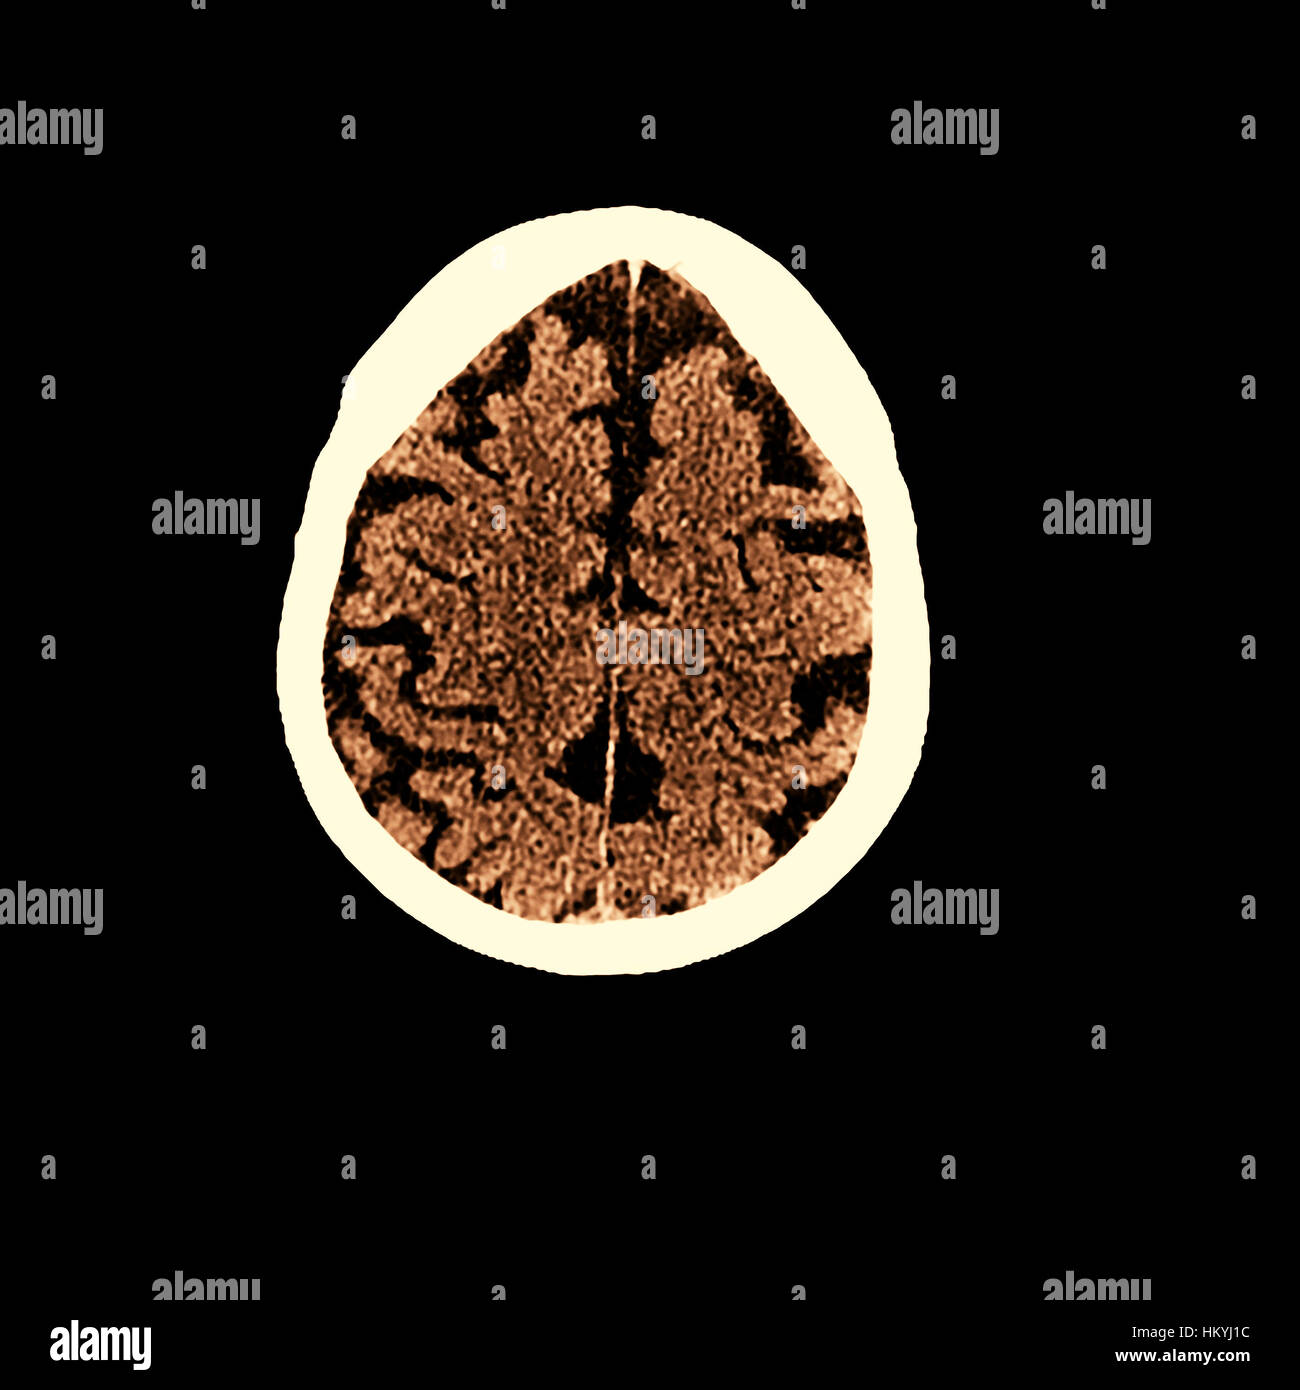

Can Ct Scan Detect Alzheimers – Dementia Talk Club

a An example brain CT of multi-infarct dementia. The brain CT showed …

Ct Scan Alzheimer’s Vs Normal – DementiaTalkClub.com

Dementia brain ct hi-res stock photography and images – Alamy

Dementia brain ct hi-res stock photography and images – Alamy

Dementia brain scan hi-res stock photography and images – Alamy